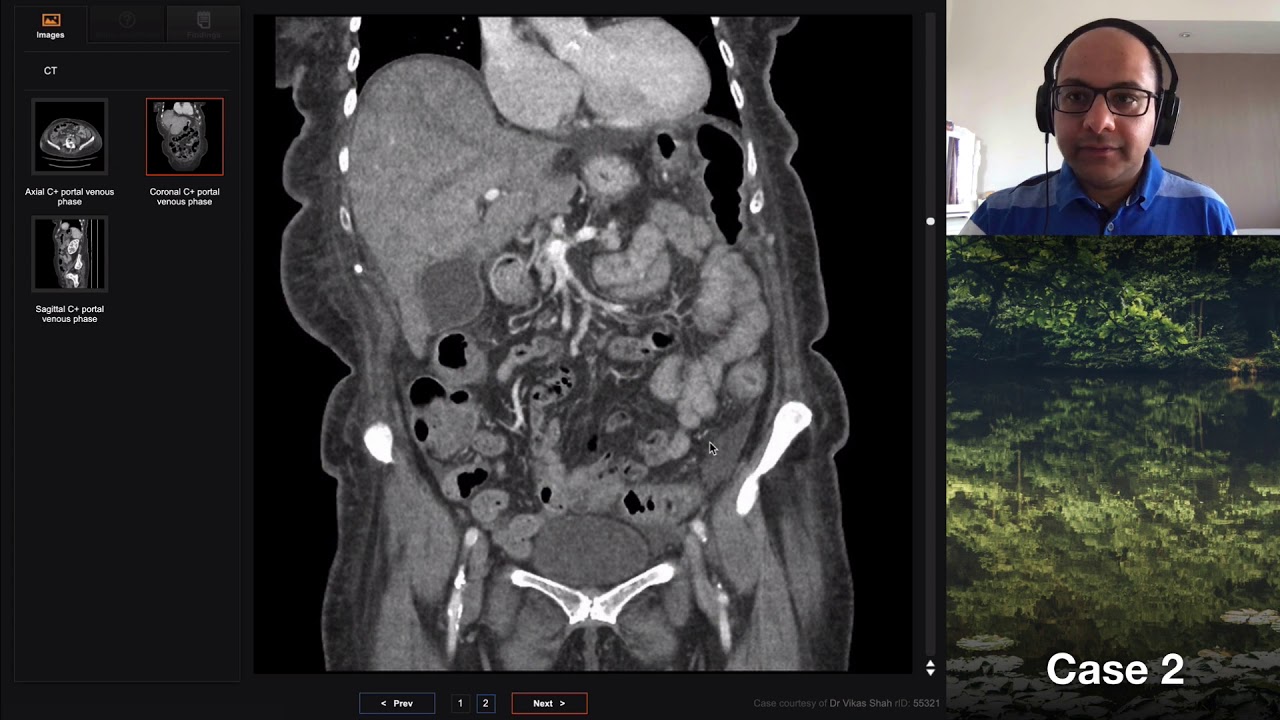

CT Colon CA Discussion

Detailed discussion of a CT revealing colon carcinoma with bone metastases.